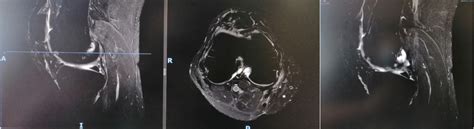

Getting a Diagnosis: How Doctors Figure It Out

Okay, guys, so you’ve got some suspicious symptoms, and you’re thinking,